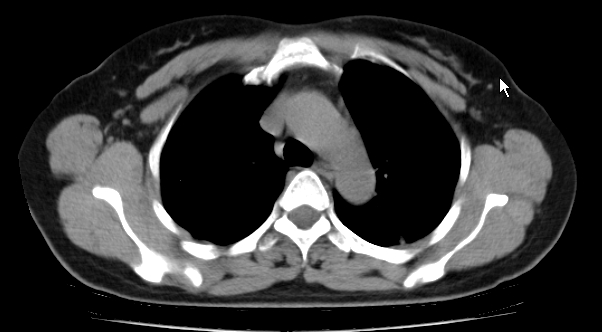

标题: CT25227:背部疼痛伴双侧胸壁痛2月,食欲差。 [打印本页]

标题: CT25227:背部疼痛伴双侧胸壁痛2月,食欲差。

肺结核并胸椎结核?请各位高手指教。

用椎体的条件来扫胸椎呀!考虑1左侧胸膜小结节形成2椎体结核并冷脓肿形成

考虑胸椎结核并椎旁软组织肿胀。

支持!不排除骨原发淋巴瘤肺内转移。

食道癌并胸椎及肺内转移